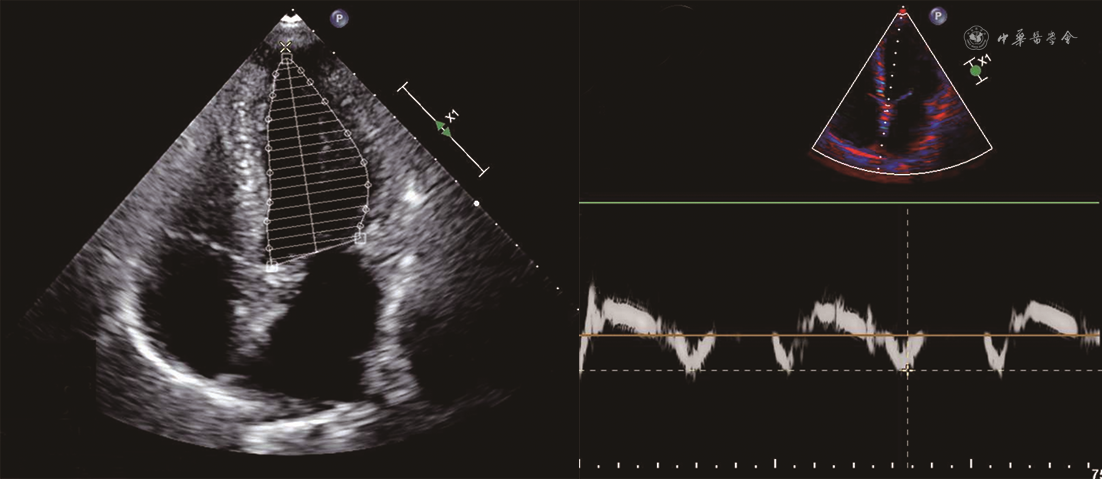

患者男,68岁,主因“胸痛、后背痛1 d”于2019年12月25日入院。患者有支气管哮喘病史,长期口服孟鲁司特。否认系统病史,否认食物、药物过敏史。无疫水、疫区接触史,无寄生虫接触史。入院体格检查:体温36.2 ℃,脉搏71次/min,呼吸25次/min,血压85/45 mmHg(1 mmHg=0.133 kPa)。神清语利,查体合作。浅表淋巴结未触及肿大。双肺呼吸音粗,可闻及肺底湿性啰音。心脏律齐,各瓣膜未闻及明显病理性杂音。腹软,无压痛及反跳痛。双下肢无水肿。血常规:白细胞计数22.39×109/L,嗜酸性粒细胞绝对值16.71×109/L[参考值(0.05~0.50)×109/L]。血浆D-二聚体1 027 μg/L(参考值<500 μg/L),肌钙蛋白T 2.950 μg/L,N末端B型利钠肽原9 949 ng/L(参考值0~1 800 ng/L),C反应蛋白1.32 mg/dl,免疫球蛋白E 421 IU/ml。心电图:窦律,完全性右束支传导阻滞。超声心动图:左心室舒张末期内径(LVEDD)58 mm,左心室收缩末期内径(LVESD)42 mm,左心房前后径43 mm,右心房左右径44 mm,左心室壁节段性运动异常,二尖瓣、三尖瓣中重度反流,下腔静脉内径增宽,左心室射血分数(LVEF)为43%,肺动脉收缩压70 mmHg(图1)。冠状动脉CT血管造影(CTA):冠状动脉呈右优势型,左、右冠状动脉未见有意义狭窄。给予补液、多巴胺、甲基泼尼龙静脉滴注以及口服甲泼尼龙等对症治疗,血压可维持在90/60 mmHg左右。2020年1月5日复查超声心动图:下腔静脉增宽,左心室壁运动普遍减弱,左心室收缩、舒张功能下降,二尖瓣轻度反流,主动脉瓣、三尖瓣轻度反流,心包积液(少量),肺动脉收缩压45 mmHg。骨髓(胸骨、髂骨)细胞学检查:粒细胞系统、红细胞系统、巨细胞系统三系增生,骨髓嗜酸性粒细胞增多。骨髓病理:骨髓增生低下,粒细胞与红细胞比例略增高,偏成熟为主,巨核细胞数量正常,形态未见特殊,可见散在嗜酸性粒细胞,稍多。基因检查报告:未检测到FIP1L1/PDGFRα融合基因,未检测到PDGFRβ、PGFR1、TEL-ABL1基因重排,未检测到JAK2基因分离重排。患者症状好转,生命体征平稳出院。出院诊断:特发性嗜酸性粒细胞增多症,Löeffler心内膜炎,心律失常(完全性右束支传导阻滞),纽约心脏协会(NYHA)心功能Ⅱ级、肺动脉高压、支气管哮喘。出院后口服甲泼尼龙片半年。出院后5个月随访,患者血常规正常,2020年5月28日复查超声心动图示LVEDD 57 mm、LVESD 42 mm、左心房前后径35 mm、右心房左右径41 mm、左心室壁节段性运动异常、二尖瓣和三尖瓣轻中度反流、LVEF为54%、肺动脉收缩压30 mmHg(图2)。2020年6月12日完善心脏磁共振检查,可见心脏饱满,左心室游离壁心肌变薄,以乳头肌至心尖水平外侧壁为著,右心室心肌形态未见明确异常,左、右心室收缩及舒张功能未见明确异常。钆对比剂延迟强化(LGE)见左心室心内膜区多发斑点状,二尖瓣、三尖瓣未见明显反流信号,提示左心室心肌弥漫性损伤,符合Löeffler心内膜炎表现(图3)。考虑心脏重构有加重趋势,除继续给予口服甲泼尼龙片外,加用沙库巴曲缬沙坦(ARNI)抑制心脏重构。出院后9个月(2020年9月21日)再次复查超声心动图(图4):LVEDD 50 mm,LVESD 35 mm,左心房前后径34 mm,右心房左右径37 mm,左心室壁节段性运动异常,二尖瓣、三尖瓣轻度反流,LVEF 56%,肺动脉收缩压30 mmHg。